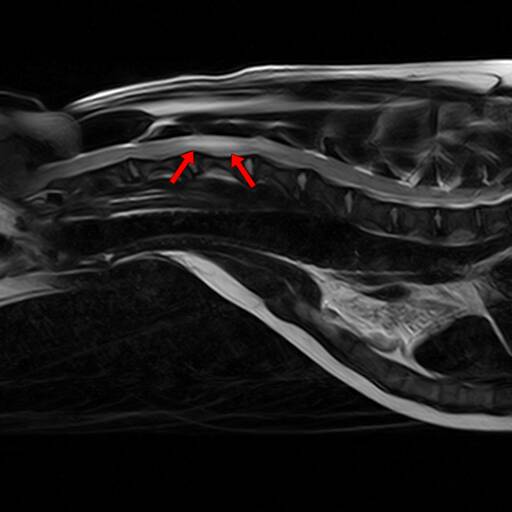

2.脊髓病变

椎间盘疾病:椎间盘突出( HansenⅠ型,急性压迫脊髓)、椎间盘突出(HansenⅡ 型,慢性压迫)、椎间盘钙化等;

椎间盘突出(图一) 椎间盘突出(图二)

诊断价值:MRI可精准定位压迫位置(如颈椎 C2/C3、腰椎 L4/L5等)、判断脊髓水肿 / 出血程度,避免 X 线 / CT 对软组织显示不足的缺陷(如 CT 难以区分脊髓水肿与肿瘤)等。